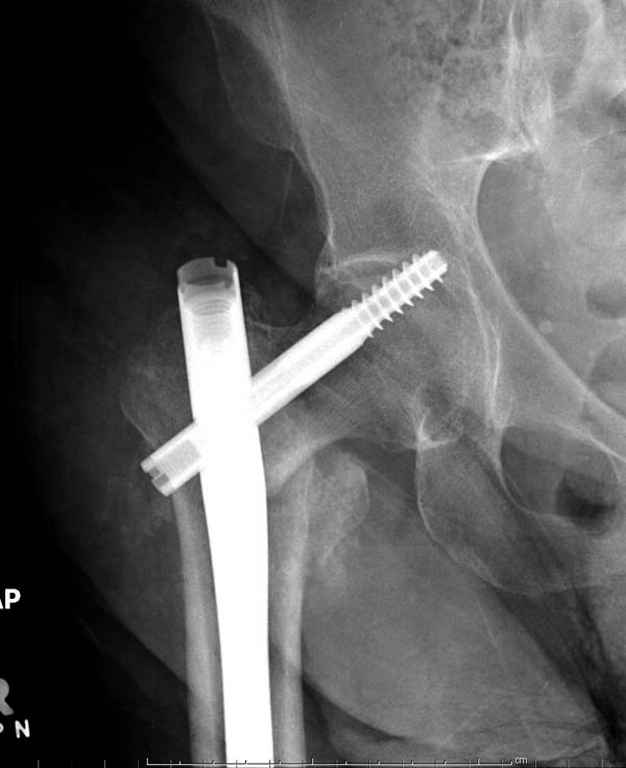

Перелом тут больше подвертельный. Нагрузка без торцевого упора на уровне перелома привела к телескопированию отломков на стержне. Ну и варус небольшой тоже свою лепту внес - если бы его не было, контактирующие латеральные стенки обоих отломков предотвратили бы укорочение, да и срослось бы за пару месяцев. А раз не срослось, упора отломков нет, более слабым местом оказались не нижние винты, а кость в головке и шейке. Так что надо было хотя бы удалить нижние винты до начала полной нагрузки.

На мой взгляд, причиной телескопирования явилось несоответствие диаметра гамма нэйл с диаметром канала подвертельного отдела бедра: обратите внимание на величину протрузии шеечного винта и величину медиализации дистального фрагмента - они одинаковы, смещение или телескопирование фрагментов происходило до того момента, пока гамма нэйл не упёрся в медиальный кортекс и образовалось пространство между латеральным

кортексом и латеральной поверхностью гвоздя.

Здраствуйте. По данному снимку видно 2-а основных момента которые привели к протрузии винта в вертлужную впадину: 1) шеечный винт дистальной поверхностью наружнего края "зацепился" за латеральный кортикал бедра, это не дало сработать динамической системе гвоздь-винт. 2) лучьше шеечный винт проводить ближе к дуге Адамса, там болееплотная костная ткань. Решенее: как подготовка к эндопротезированию, реостеосинтез, можно такой же системой, но с учетом упомянутых моментов, максимальное безнагрузочное ЛФК (без боли).